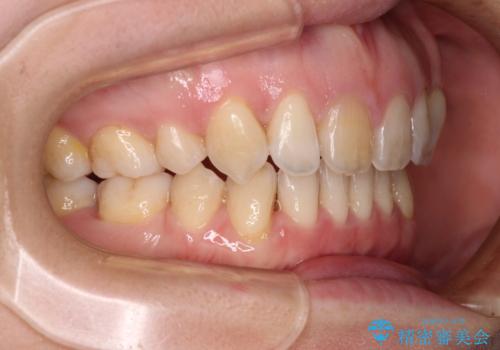

- 上の前歯の飛び出した感じを改善したいとのことで来院された患者様です。

上顎左右第一小臼歯2本、下顎左右第二小臼歯2本を抜歯し、ワイヤー装置にて口元を引っ込めるよう矯正治療を行うこととしました。

上下の前歯に隙間が空くほど上顎前歯が前に飛び出していましたが、抜歯矯正により上下前歯がぴったりと付くほど口元を引っ込めることができました。